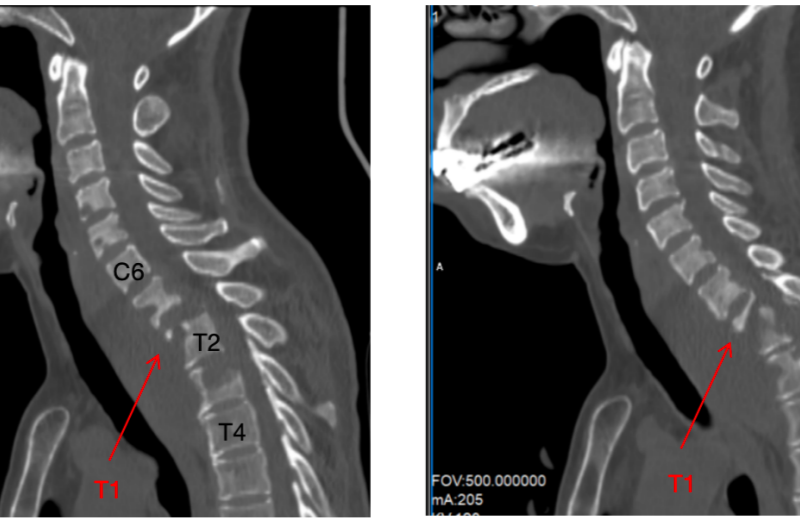

颈部剧痛莫轻视!女子颈椎结核致截瘫,骨头被细菌“啃掉”90%